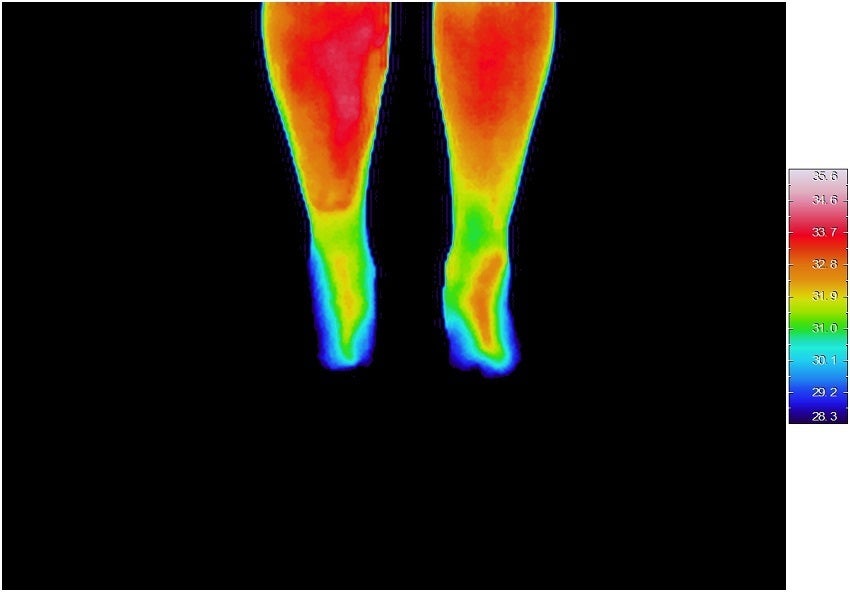

血流やリンパの流れを活性化するために、4枚重ねて靴下を履いてデトックスする!なんていう話を聞いたことがあります。それも、1足目はシルク、2足目は綿、3足目はまたシルク、4足目は綿。これだけ重ねれば温かくなると思いますが範囲はつま先から足首までです。脚全体が温まるまでには時間がかかります。シルクは、その構造からして空気を溜めやすい構造になっています。そのシルクがお腹までの長さのソックスなんて聞いたことがないと思います。それも起毛している訳ですから、体温を含んだ空気の層が厚くなっています。睡眠するときにも、靴下を履いたまま寝る人がいます。ほとんどの人が、睡眠中に脱いでしまいます。それって、睡眠中のストレスです。できれは、寝床内温度は約33度で一定の方が良いです。ビッグソックスを履いて寝ると布団に入るとすぐに足の温度が上がり始めて何と4分後には約33度になっています。【下図参考】その後は1時間かけて約35度まで上昇しています。シルクが温度を上げているのではなくてその人の体温を温存しているのですから、人の平熱=約36度以上にはなりません。また、温度が上がると乾燥しますから水分がなくなります。睡眠中とはいえ、お肌には大敵です。しかし、シルクが空気中から水分を補給してくれるのです。温かく眠れて、朝起きたときはお肌がしっとり。シルクの力です。